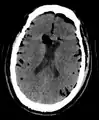

| Pneumocephalus and comminuted fracture of the frontal sinus |

Pneumocephalus is the presence of air or gas within the cranial cavity. It is usually associated with disruption of the skull: after head and facial trauma, tumors of the skull base, after neurosurgery or otorhinolaryngology, and rarely, spontaneously. Pneumocephalus can occur in scuba diving, but is very rare in this context.

CT scans of patients with a tension pneumocephalus typically show air that compresses the frontal lobes of the brain, which results in a tented appearance of the brain in the skull known as the Mount Fuji sign.[1][2][3] The name is derived from the resemblance of the brain to Mount Fuji in Japan, a volcano known for its symmetrical cone. In typical cases, there is a symmetrical depression near the midline (such as the crater of a volcano), due to intact bridging veins.[3] Its occurrence seems to be limited to tension pneumocephalus (not occurring in pneumocephalus without tension).[4] The sign was first described by a team of Japanese neurosurgeons.[5]